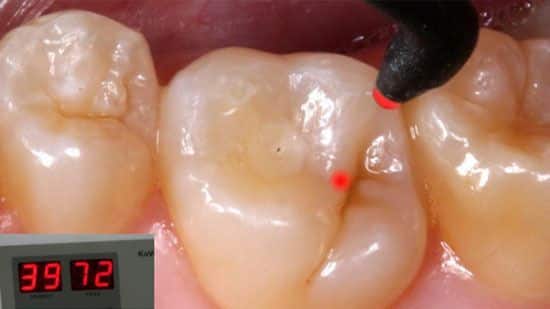

Diagnodent. Detecting caries by laser

The Diagnodent system diagnoses the presence of caries using a laser. It consists of a laser beam that shines on the tooth and measures the tissues’ different levels of fluorescence. The technique is quick, the patient feels nothing at all (we simply illuminate the tooth) and it provides data on the activity of caries in the area.

This not only allows us to detect hidden caries, but we can also appreciate how advanced, active or aggressive they are and then treatment them accordingly.

The Diagnodent laser caries diagnosis system facilitates early detection of hidden tooth damage